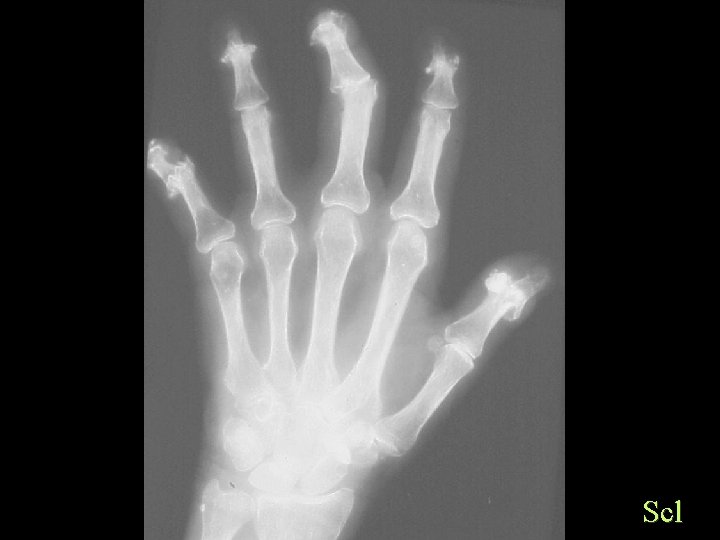

Scleroderma • Hands and pressure areas • Acro-osteolysis • Soft tissue changes • Subluxations

Scl

Calcification By site Finger Tips • • Scleroderma CREST Dermatomyositis Trauma